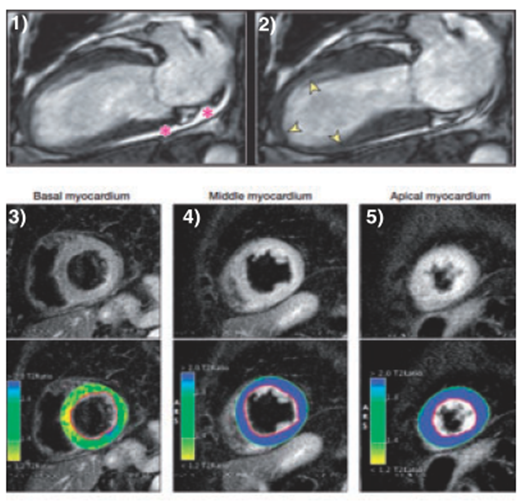

➤ CMR

• 心肌炎:室壁运动异常的类型通常不同,功能的恢复心肌炎通常比Takotsubo综合征患者更慢,CMR可以作为鉴别方法。